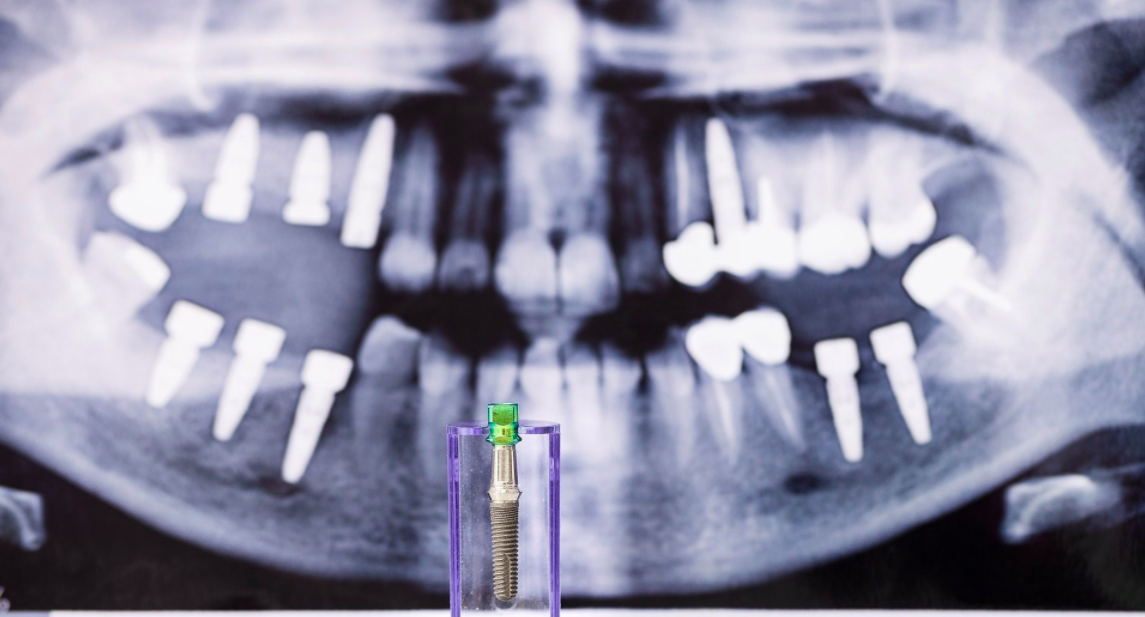

– Un trattamento del canale radicolare eseguito correttamente salva un dente, che altrimenti dovrebbe essere estratto e successivamente sostituito da un impianto dentale o da un lavoro dentale. Negli ultimi anni, il miglioramento dei metodi di trattamento endodontico ha portato a una riduzione del numero di denti estratti. Sempre più denti distrutti o infetti vengono mantenuti sull’arco oggi, a causa delle prestazioni ottenute dai trattamenti canalari.

Con l’aiuto di strumenti moderni, si ottiene un ampliamento più accentuato del canale e una pulizia nettamente superiore e con i nuovi materiali di tenuta si ottiene un riempimento del canale perfettamente sigillato. La lunghezza del canale è ora misurata elettronicamente, quindi il medico sa esattamente fino a che punto ha raggiunto il riempimento del canale. Un isolamento più efficiente del dente assicura una prognosi a lungo termine molto migliore, poiché non esiste contaminazione intra operatoria con la saliva.